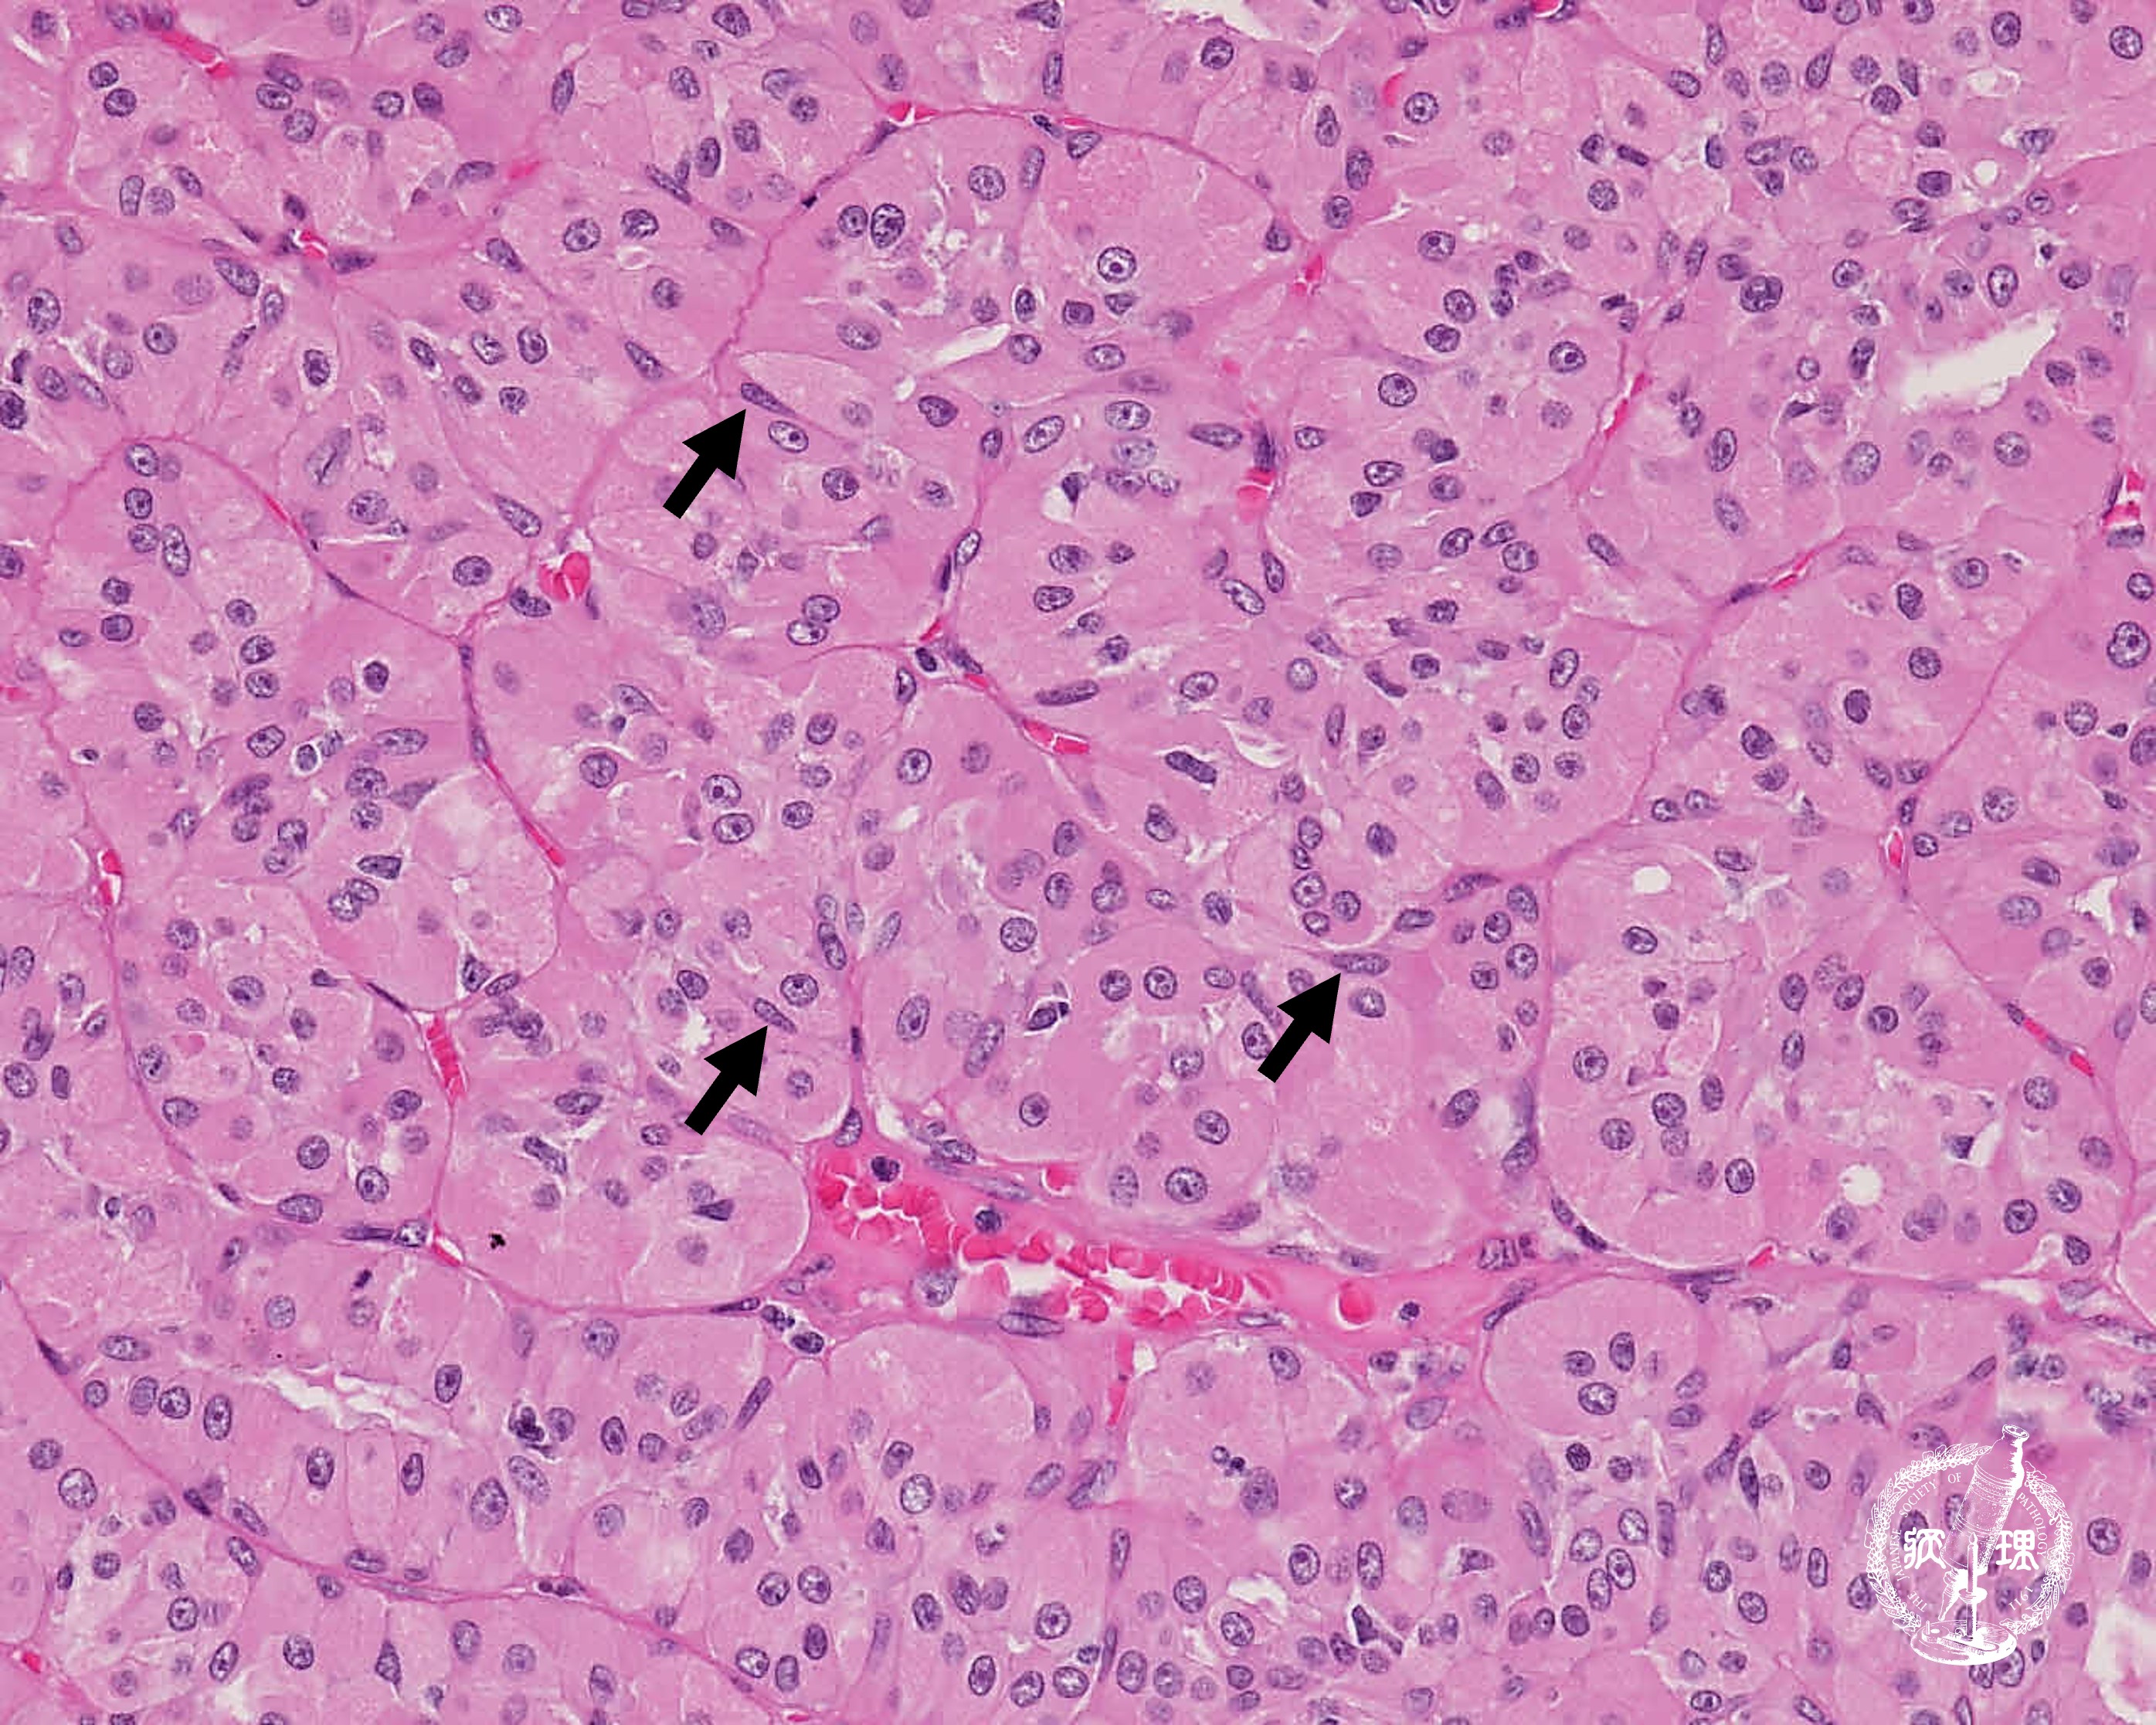

ミクロ像(HE強拡大):好酸性の豊富な細胞質を有する細胞(light cells)が胞巣状構造を呈し増殖している。細胞質の好酸性がより強く、核が濃縮状の細胞(dark cells)も散在性に混在する。腫瘍細胞間の間質は狭く、毛細血管が介在する。

• 唾液腺腫瘍 (オンコサイトーマ)